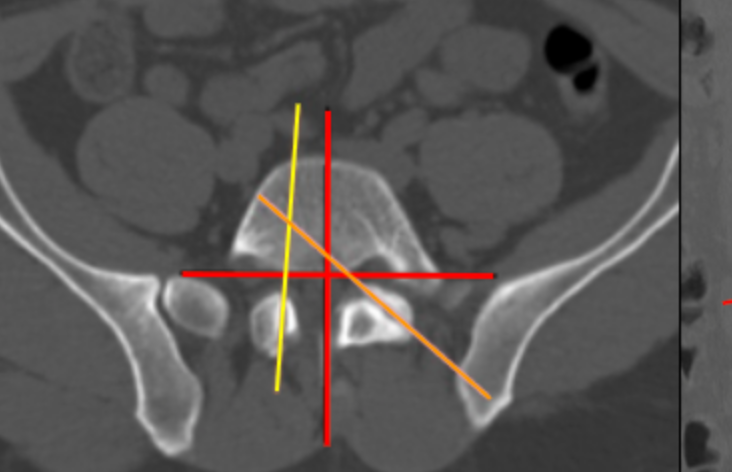

Sacral Morphometry

Facet Join Orientation and Tropism

Axial Rotation